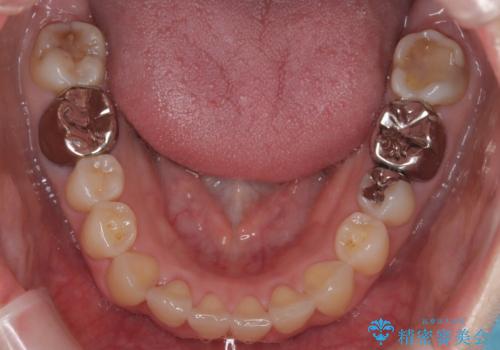

- 前歯の翼状捻転の改善を希望してこられた患者様です。

下顎の叢生はインビザラインで解決することがきましたが、上顎の捻転が完全には改善できなかったため、上顎は途中からワイヤーを用いて治療を行っています。

捻転の改善はインビザラインで苦手とするところですので、うまく治らない場合はワイヤーを提案しています。